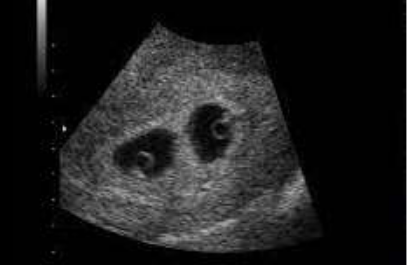

Paciente com 32 semanas de idade gestacional foi encaminhada para realização

de ultrassonografia obstétrica, onde aparentemente observa-se uma placenta, dois fetos e duas cavidades amnióticas. Ela realizou um exame de ultrassom com 7 semanas de gestação em consultório, porém só possui as imagens.

Com base na foto abaixo, assinale a afirmativa correta: